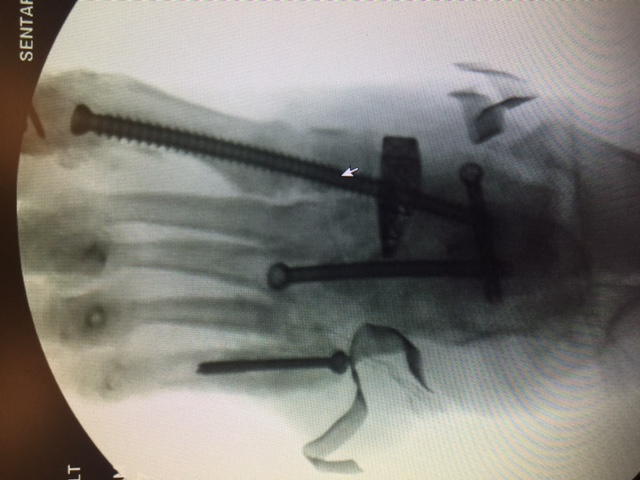

Additional emerging concepts with regard to beaming within our institution include the use of titanium trusses for cases involving significant midfoot bone loss. We have performed several of these reconstructions with good long-term limb salvage results. Structurally speaking, titanium trusses accept and resist the same loads as beams. A benefit of a truss is the bending stiffness and bending strength is a factor of 4 or above the structural mass required for the midfoot, which can easily resist failure.

In our experience, the mechanical forces of the midfoot in compression are enough to place the wedge without the need for fixation. However, we have routinely delivered beam screws through the titanium cage. We believe the truss acts as an additional load-bearing device with an independent section modulus that substitutes for the midfoot bone. When working in combination with a beam, we believe that the truss deflects forces from the beam.

Additionally, the titanium truss is filled with autogenous bone graft and orthobiologics, allowing for incorporation through the osteotomy site. This device allows for reconstruction in situations of excessive bone loss, acting as a replacement with the capacity for ingrowth. Follow-up demonstrates improved angular deformity correction with complete bridging on computed tomography (CT) scan.